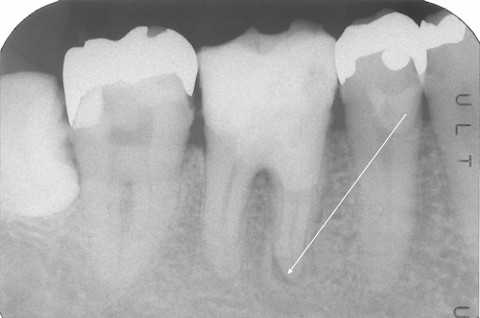

伝説の根管治療法4(Per+GA、3MIX+α-TCP) 2025.10.27

伝説の根管治療法3(Per+GA、3MIX+α-TCPの… 2025.09.08 コメント(7)